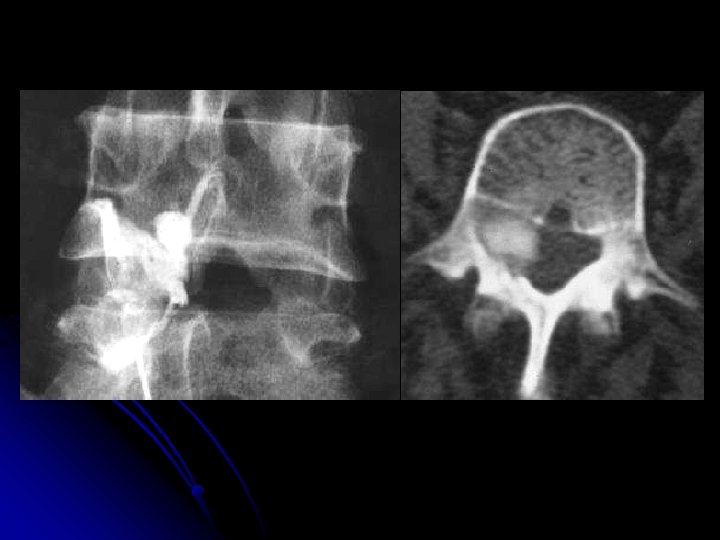

MYELOGRAPHIE l Bilan pré-chirurgical d’une sténose canalaire l Hernie discale mobile ou dynamique l IRM: l Contre indiquée l Non disponible

MYELOGRAPHIE l opacification des espaces sous arachnoïdiens l produit de contraste non ionique l Examen invasif: milieu neurochirurgical l Précaution: l Asepsie l Deux clichés du rachis lombaire de face et de profil l Prélèvement du LCR: étude cyto-chimique.